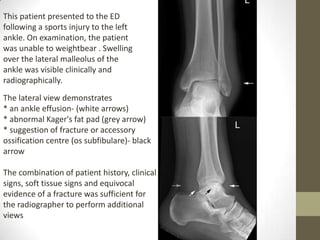

This patient presented to the ED

following a sports injury to the left

ankle. On examination, the patient

was unable to weightbear . Swelling

over the lateral malleolus of the

ankle was visible clinically and

radiographically.

The lateral view demonstrates

* an ankle effusion- (white arrows)

* abnormal Kager's fat pad (grey arrow)

* suggestion of fracture or accessory

ossification centre (os subfibulare)- black

arrow

The combination of patient history, clinical

signs, soft tissue signs and equivocal

evidence of a fracture was sufficient for

the radiographer to perform additional

views